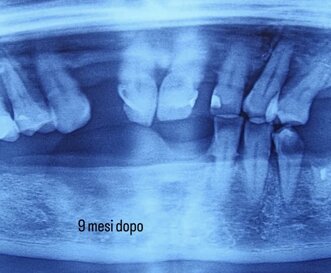

INNESTO OSSEO

Innesto osseo con biomateriale osteoconduttivo impiegato per la rigenerazione ossea alveolare, finalizzato a ripristinare volume e supporto strutturale per elementi dentari o impianti."

Come visibile nell'immagine , a 9 mesi dall' innesto osseo, abbiamo recuperato lo spessore osseo , che favorisce il posizionamento degli impianti dentali.

I biomateriali impiegati possono essere di origine naturale (autogeni) o sintetica e favoriscono la formazione di nuovo osso, creando una base solida per l’inserimento di impianti dentali.

POSIZIONAMENTO IMPIANTI DENTALI

A 9 mesi dall'intervento è stato possibile posizionare gli impianti dentali, grazie allo spessore recuperato.

L’innesto osseo con biomateriali è una tecnica avanzata utilizzata in odontoiatria e implantologia per rigenerare il tessuto osseo in aree con insufficiente volume.